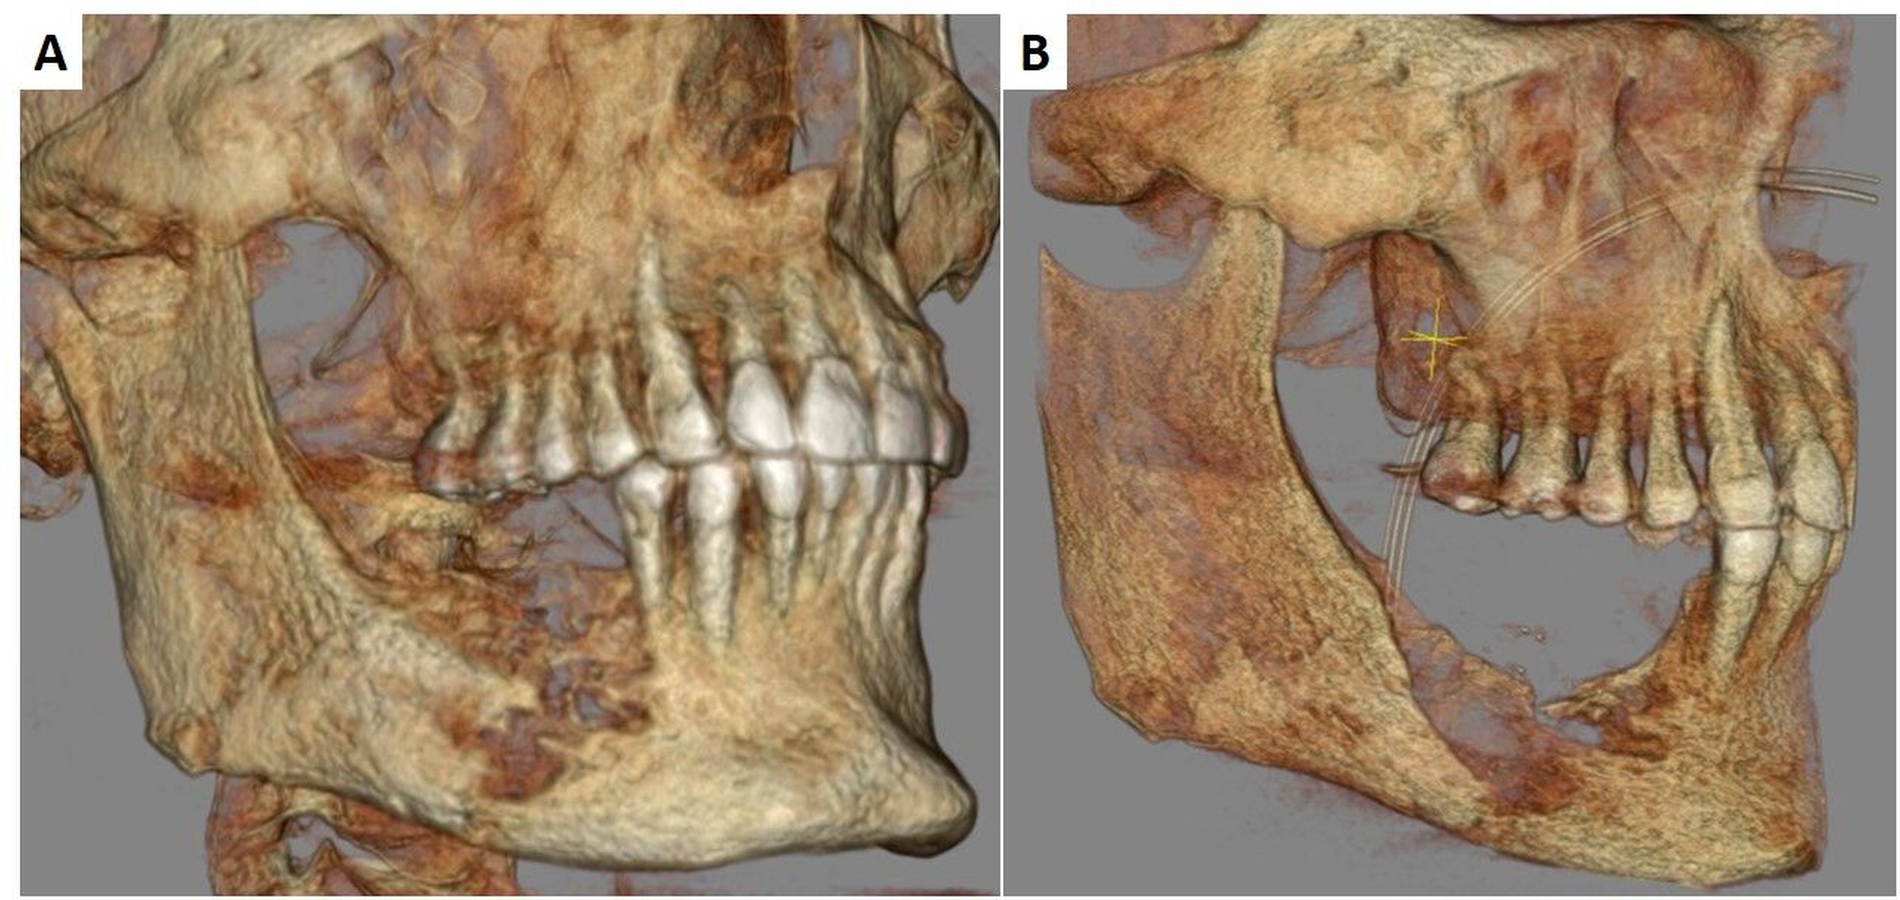

Die Operation konnte am Folgetag komplikationslos in Intubationsnarkose durchgeführt werden. Bei ausreichender Reststabilität des Unterkiefers wurde auf eine osteosynthetische Versorgung verzichtet (Abbildung 4). Die histopathologische Nachuntersuchung der intraoperativ gesammelten Knochenproben bestätigte die Verdachtsdiagnose einer sekundär chronischen Osteomyelitis. Es zeigten sich eine chronisch granulierende Entzündung der Schleimhaut sowie eine floride granulozytäre Infiltration der Markräume des erfassten kompakten Knochengewebes.

Diese Verdachtsdiagnose wurde allerdings bei regelrechten Untersuchungsbefunden nicht bestätigt. Nach reizloser Abheilung der Wunden konnte der Patient in die ambulante Nachbehandlung entlassen werden. In den bisher durchgeführten Nachkontrollen über vier Monate zeigte sich ein beschwerdefreier Patient mit enoral stabilen und reizlosen Lokalverhältnissen. Dennoch ist bei Auftreten eines Rezidivs oder einer pathologischen Unterkieferfraktur eine Unterkieferkontinuitätsresektion mit mikrovaskulärer Rekonstruktion unumgänglich.